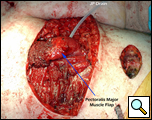

Eleven months later, he presented with a several month history of a painful fixed, firm mass over the pectoral area of the left chest and a smaller mass inferior to this (Figure 1). CT scan demonstrated a new 2 cm nodule in the left upper lobe associated with an anterior chest wall mass six centimeters in size in addition to bilateral new pulmonary nodules (Figure 2). The mass was tethered to the skin and in danger of eroding through it. The patient underwent en-bloc resection of the chest wall and adjacent lung (Figures 3a-c). The resulting defect (Figure 4a) was reconstructed with 2 mm Gore-Tex patch (Figure 4b) and pectoralis major muscle flap (Figure 4c) with primary skin closure (Figure 4d). The pathology revealed metastatic chordoma (Figures 5a-d). The patient recovered well, leaving the hospital on the sixth postoperative day.

The appropriate treatment for chest wall metastases for chordoma is not known due to the rarity of this occurrence. Indications for chest wall metastasectomy include resection for diagnosis, local control, and palliation / prevention of skin ulceration and rarely for cure or as part of a multidisciplinary approach [7]. While radiation therapy is another option for local control, its ability to prevent progression of disease is unpredictable and unknown in the case of chordoma. Once the area of the chest wall has been irradiated, subsequent resection and reconstruction is more difficult and prone to failure [8, 9]. In the presented case, resection was performed for local control, pain relief and to prevent the complications of ulceration, necrotizing infection and bleeding from a tumor eroding through the anterior chest wall. The principles of chest wall resection were adhered to by performing a full thickness en-bloc resection of the mass, reconstruction with a two mm Gore-Tex patch and coverage with a well-vascularized myocutaneous flap.